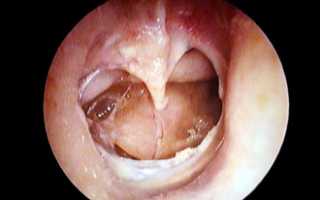

- Миринготомия — процедура, при которой в барабанную полость вводятся тонкие трубки для отведения серозного содержимого из среднего уха. В процессе заживления трубки естественным образом вытесняются из слухового прохода до полного удаления.